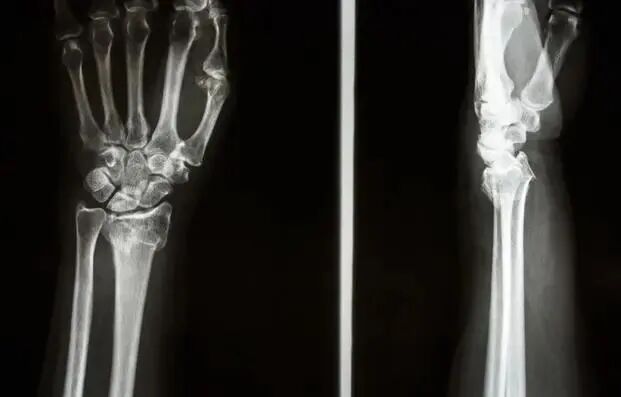

老年人普遍有骨质疏松症,骨质疏松症引起的骨折在日常诊疗过程中随处可见。其中,手腕骨折最常见的是桡骨远端骨折。

桡骨远端骨折(fractureofdistalendofradius),指距桡骨远端关节面3cm内骨折。它是上肢最常见的骨折部位。这种损伤约占急诊科骨折的1/6。桡骨远端骨折多为两类人群中的孤立性骨折:运动中高动能跌倒的年轻人和低动能跌倒的骨质疏松老年人。因为这部分是松质骨和皮质骨的交界处,为了解剖薄弱部位,一旦受到外力打击,很容易骨折。